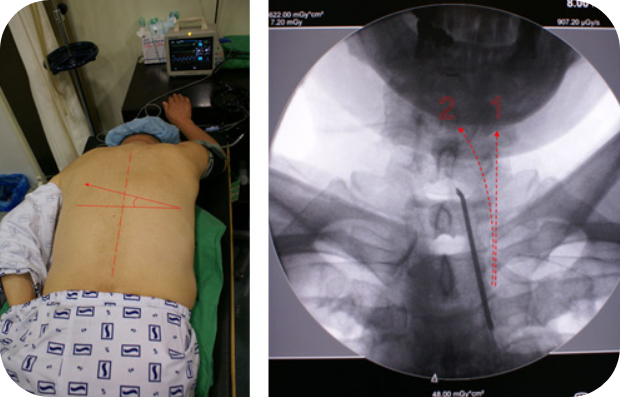

시술 방법은 1mm 굵기의 얇은 관을 삽입한 후 척추신경관과 신경 사이의 공간을 통해 디스크와 신경의 염증이 있는 부위에 도달한 후에 유착 방지제와 염증을 없애주는 약물을 주입하게 됩니다. 시술을 통해 척추신경으로 돌출된 디스크의 부종을 없애 신경의 압박을 풀어주고 척추신경을 정상적인 상태로 회복시켜 유착을 제거함으로써 신경 주변의 혈액순환을 개선하여 디스크를 치료하게 됩니다.